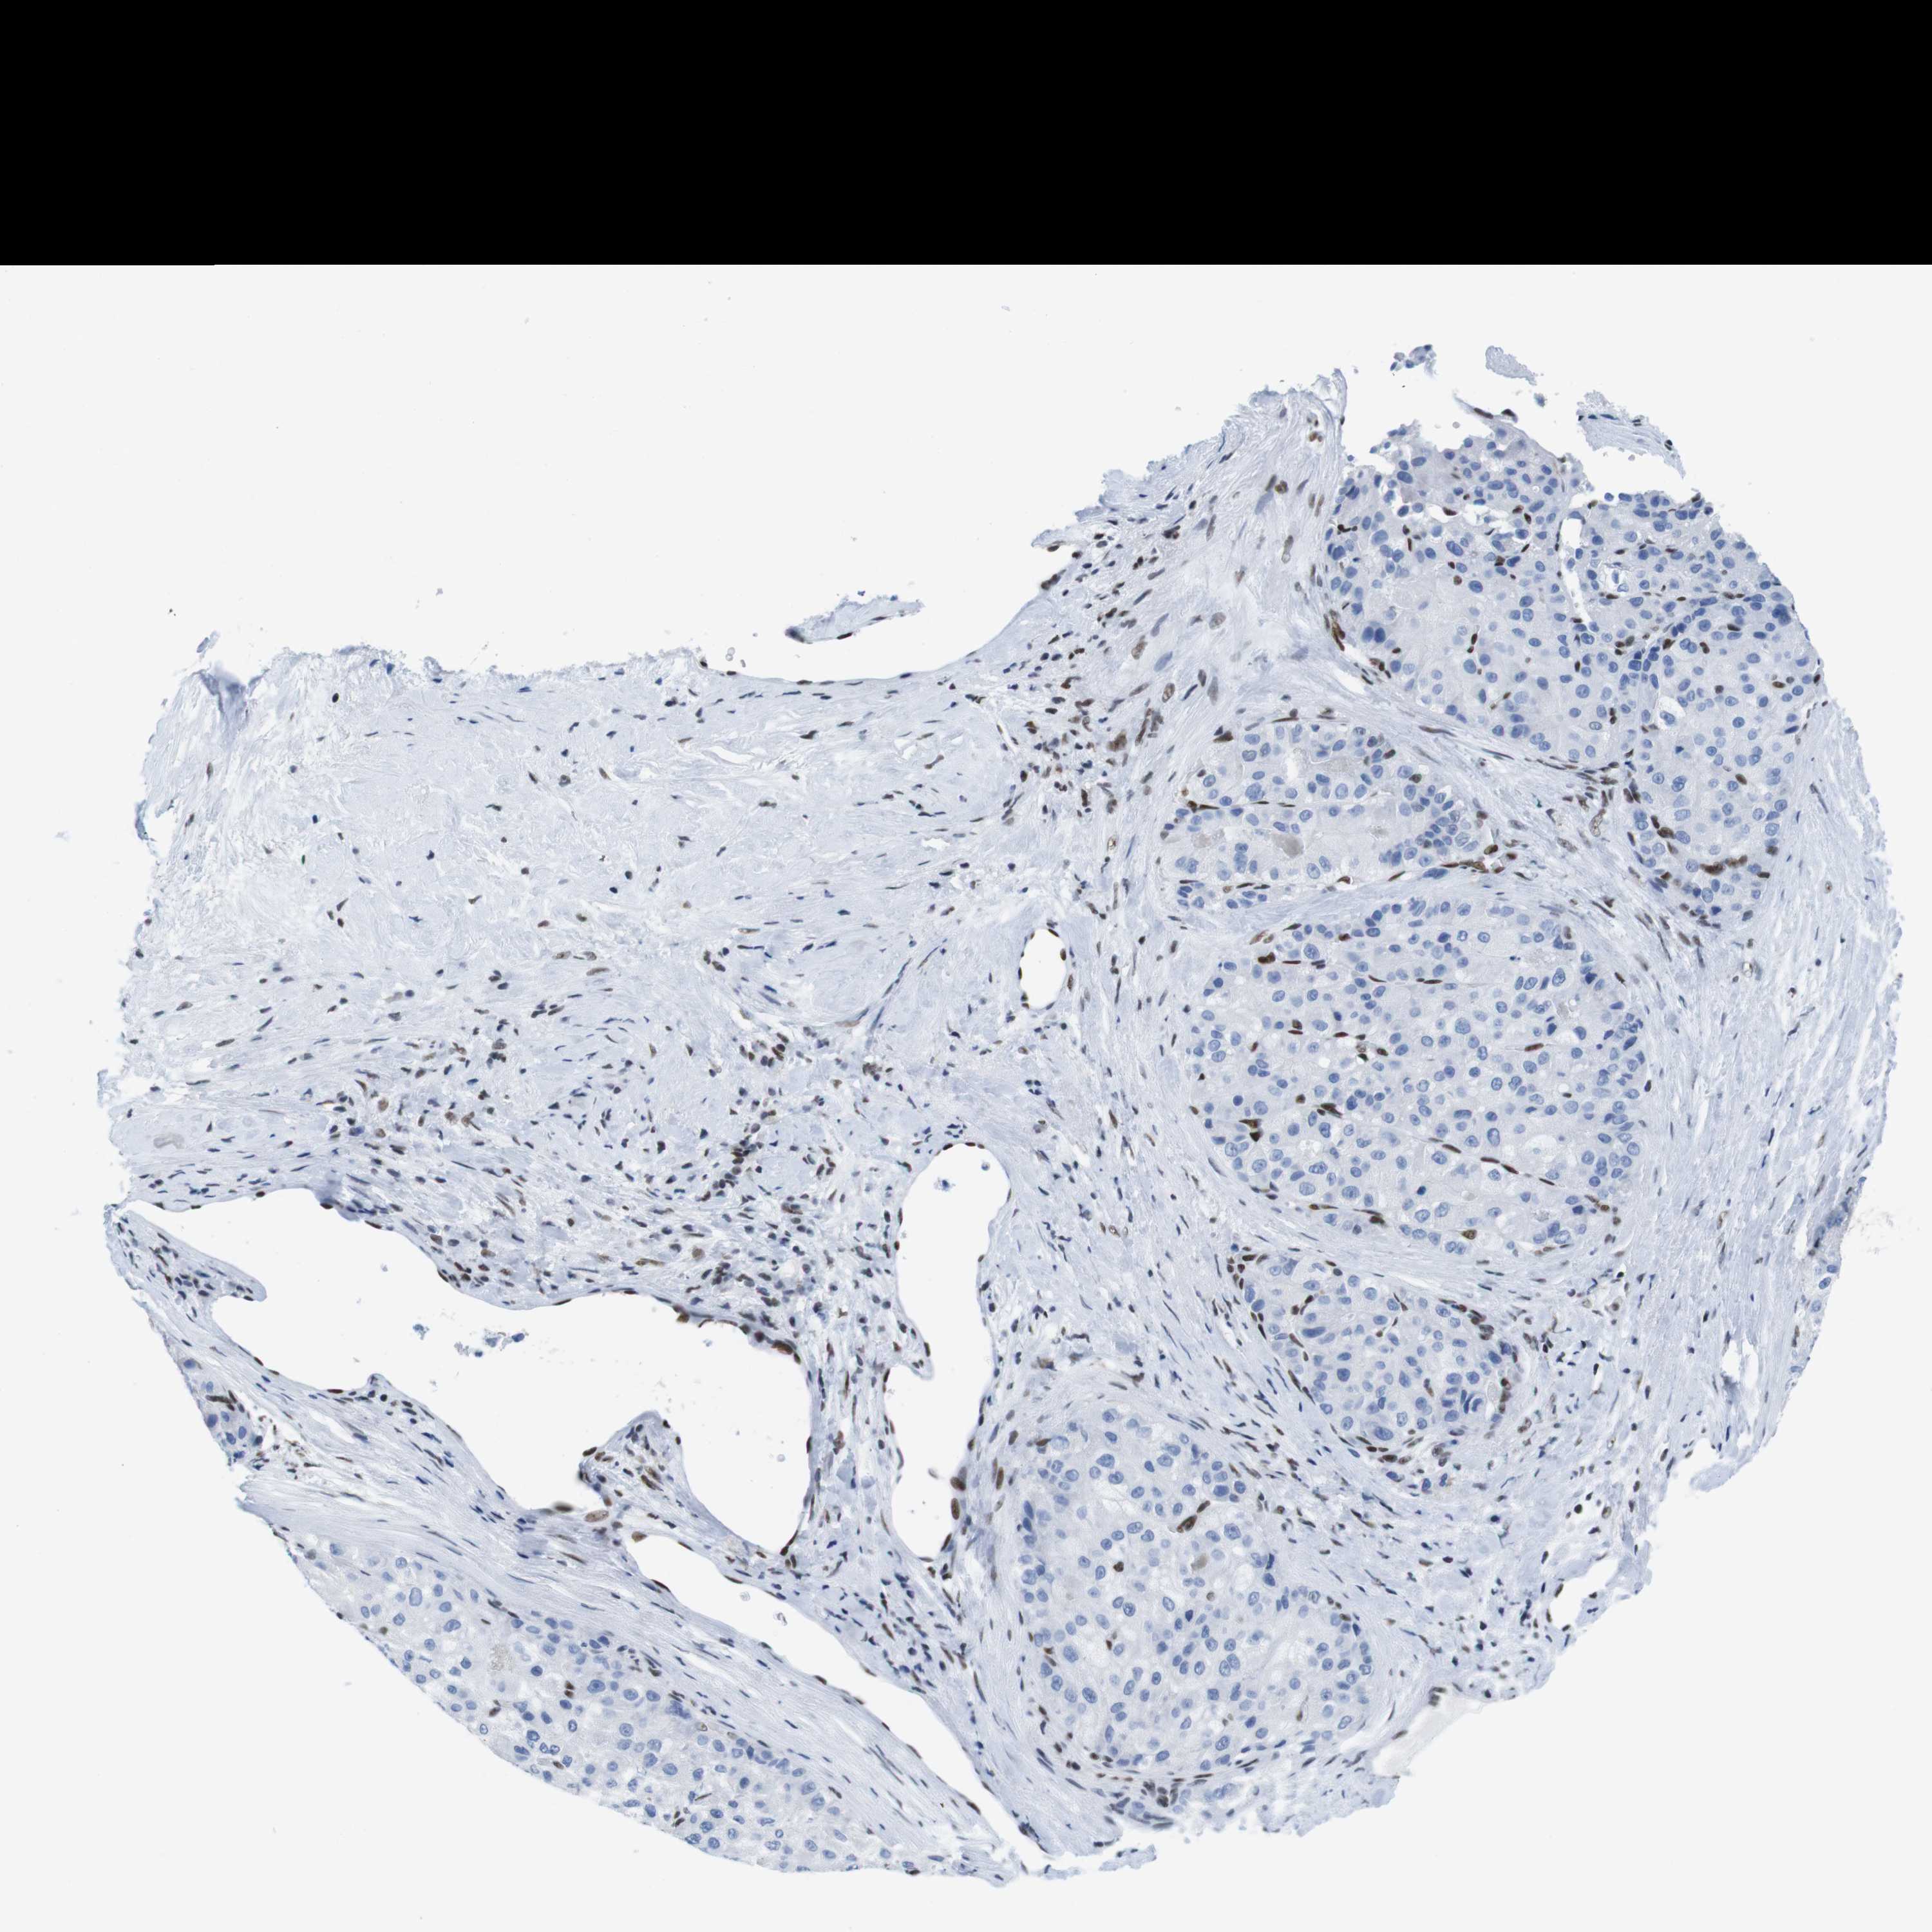

LIVER CANCER - Protein expressioni

A mouse-over function shows sample information and annotation data. Click on an image to view it in a full screen mode. Samples can be filtered based on level of antibody staining by selecting one or several of the following categories: high, medium, low and not detected. The assay and annotation is described here.

Note that samples used for immunohistochemistry by the Human Protein Atlas do not correspond to samples in the TCGA dataset.

Antibody stainingi

Antibody staining in the annotated cell types in the current human tissue is reported as not detected, low, medium, or high, based on conventional immunohistochemistry profiling in selected tissues. This score is based on the combination of the staining intensity and fraction of stained cells.

Each image is clickable and will lead to virtual microscopy that enables deeper exploration of all samples and also displays staining intensity scores, fraction scores and subcellular localization as well as patient and tissue information for each sample.

Antibody HPA002134

Antibody CAB016293

Staining

High

Medium

Low

Not detected

Intensity

Strong

Moderate

Weak

Negative

Quantity

>75%

75%-25%

<25%

None

Location

Nuclear

Cytoplasmic/membranous

Cytoplasmic/membranous,nuclear

Cholangiocarcinoma

Carcinoma, Hepatocellular, NOS